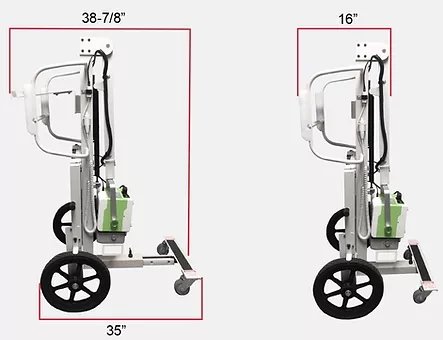

- Lightweight: 100 pounds

- Compact: 26” Wide x 53" High x 39" Deep